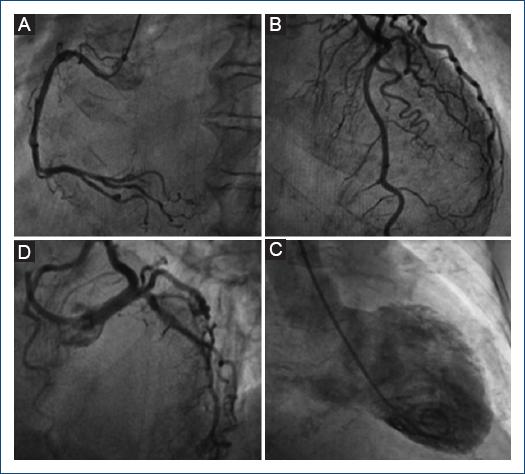

A 75-year-old female with a lymphoma record, diabetes mellitus 2, and hypertension, was hospitalized in another institution with a diagnosis of urosepsis; she required vasopressor treatment and a 3rd generation cephalosporin 2 weeks ago with a partial clinical improvement; but two weeks later she returned to the same hospital with dyspnea and peripheral edema. At the physical examination highlights general rales and peripheral edema, an electrocardiogram (ECG) showed sinus rhythm with ST-segment elevation in V2-V6, DI, and aVL. The troponin I level was 620 ng per liter on a high-sensitivity assay, and she was referred to our institute. Upon her arrival to the emergency department at our insistution, she had a Glasgow score of 10 points, respiratory distress and medium blood pressure <65 mmHg. The ECG persists with a ST-segment elevation in V2-V6, DI, and aVL (Fig. 1). The patient was intubated and required invasive mechanical ventilation, we started anti-ischemic treatment and vasopressor. In the context of ST-segment elevation myocardial infarction and cardiogenic shock, she was transferred to the cardiac catheterization laboratory, where it was reported the absence of injuries in the right coronary, circumflex, and anterior descending arteries (Fig. 2). With anterior and inferior akinesia, and apical dyskinesia, suggestive of Takotsubo cardiomyopathy (Fig. 3). After that, she was transferred to the coronary care unit where the diagnosis of cardiogenic shock was integrated. We iniated treatment with an inodilator (levosimendan) and inserted an intra-aortic balloon pump (IABP) as a ventricular-assistant device. A transthoracic echocardiogram was performed, reporting basal hypokinesia, apical akinesia. LVEF 12%, without a dynamic obstruction of the left ventricular outflow tract and a lung ultrasound with a B-profile. Urine and blood culture were negative; she presented a clinical improvement, so the vasopressor and inodilator were retired and started deflating the IABP. We performed another echocardiogram obtaining a LVEF 27%. As she presented clinical improvement as the days went by, we removed the ventricular assistant device. Unfortunately, in a sudden way, the patient started with ventricular tachycardia requiring pharmacological, electrical defibrillation, and resuscitating maneuvers without a response.

The patient had three of four criteria according to the Mayo Clinic diagnostic criteria for takotsubo syndrome and 38 points of InterTAK diagnostic score. Cardiogenic shock as a presentation of takotsubo syndrome is not common, in this case, female gender and a decreased LVEF are well-known risk factors associated with takotsubo syndrome and it's complications. In addition, diabetes mellitus presents only in 12% of patients and is associated as a protective factor due to slow release of catecholamines1. Some prospective studies enhance that 50% of patients developed complications but only 2-3% died during the acute phase; being our case report part of this statistic2. In this context, patients that receive cardiac mechanical support (IABP, Impella, or extracorporeal membrane oxygenation [ECMO]) have a lower in-hospital mortality rate (12.8%) than those without cardiac mechanical support (28.3%), making this intervention a key factor in the evolution of the patients3. It is important to mention that IABP is the predominantly used mechanical support device all over the world. However, it is also established and supported by the Heart Failure Association of the European Society of Cardiology that in case of having the source and according to the clinical evolution of the patient progression of mechanical support to Impella or V-A ECMO is indicated to avoid refractory cardiogenic shock4,5. Early implantation of mechanical devices should be considered as a bridge to recovery therapy to reduce the high mortality rate during the acute phase6. Identifying more predictor data of shock valuable for an appropriate algorithm of treatment strategies are imperative6,7. According to the results of the international registry of takotsubo syndrome, identifying variables such as apical takotsubo syndrome, physical stress, lower LVEF, and atrial fibrillation should be components to include in a primary risk stratification model3.